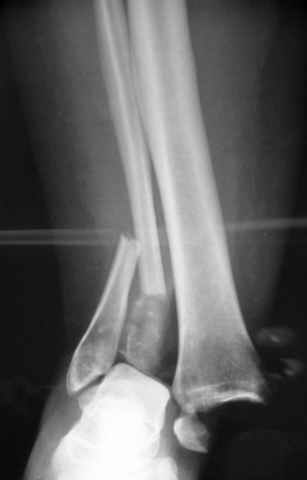

исходное

Re: ANKLE FRACTURE